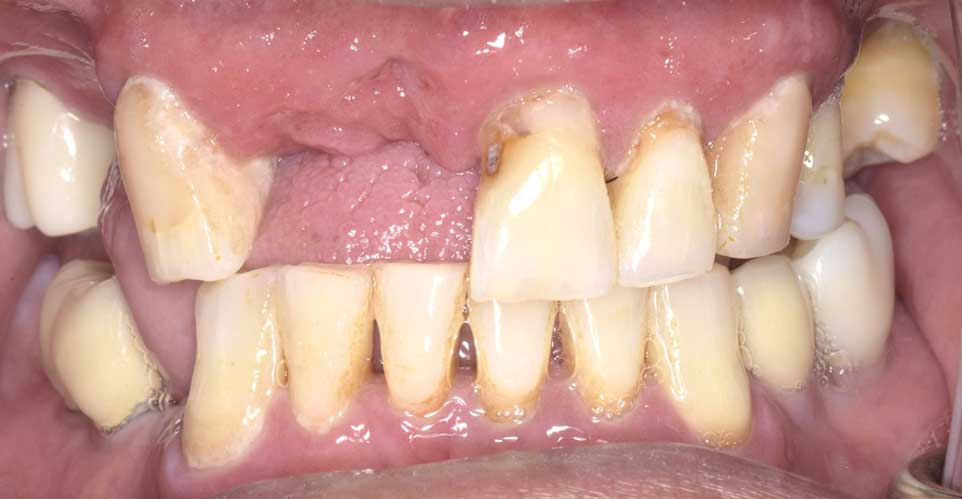

治療前

インプラント治療 オールオン4

虫歯と歯周病でボロボロになった歯の抜歯を行い、当日に4本のインプラントを埋入し,仮歯まで装着しました。